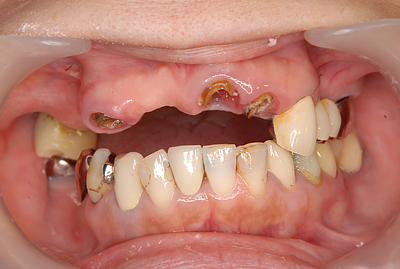

症例140代 男性 主訴 奥歯に歯を入れたい、しっかり噛みたい

治療前

治療後(5年経過)

主訴 奥歯がない為、食事が不自由である。入れ歯は煩わしいので、固定制のインプラントにして欲しいと訴え来院。口腔内全体で6本のインプラントを埋入。仮歯にて神経筋機構、顎関節のバランスを整え、リハビリを経て、約5ヶ月後にジルコニアを装着。

リスクとしては、外科的侵襲がある。デメリットは、保険外診療の為、経済的負担がある。

費用 316万(税込) (オペ・仮歯・最終補綴物まで含む)